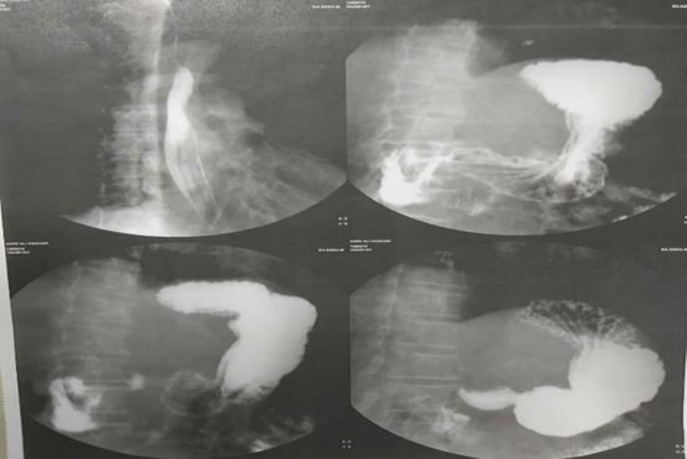

According to report of ERCP and possibility of CBD to duodenum fistula, upper GI series was done and reported no evidence of fistula (figure 2) After conservative treatment and ERCP and stent placement, he was discharged from hospital. After discharge, he presented to hospital with recurrent fever, icter, weakness and weight loss. He underwent laparotomy. Gallbladder was not seen in anatomical location (GA). CBD had fistula to gastric antrum just lower than bifurcation level of common hepatic duct that made it impossible to repair CBD after dissection. Furthermore, he had replaced right hepatic artery (figure 3) Therefore we decided to do Roux-en-Y hepaticojejunostomy.